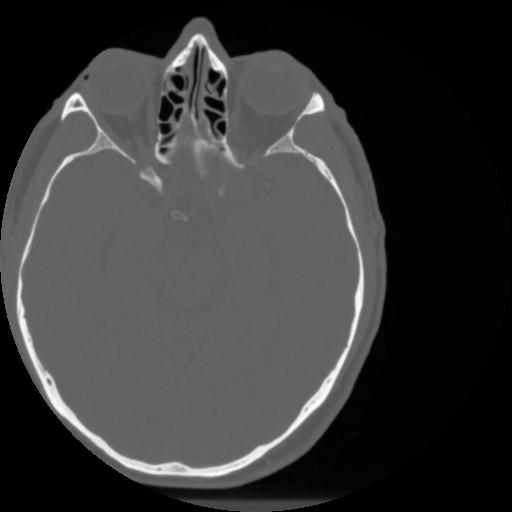

4 CEREBRO,,Vol,0.5,CEREBRO,,